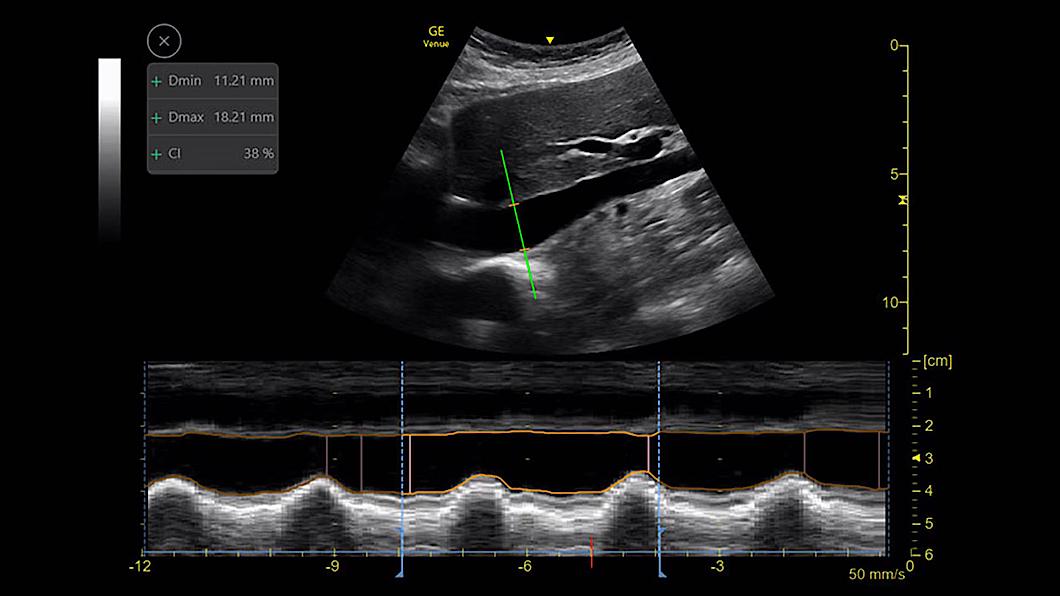

Catheter to Vessel Ratio

Sélectionner le cathéter adapté

Le choix d'un cathéter de mauvaise taille peut entraîner une thrombose liée au cathéter.2 Le rapport cathéter-vaisseau est un outil de mesure qui aide les cliniciens à choisir le cathéter de taille appropriée en fonction du diamètre du vaisseau.